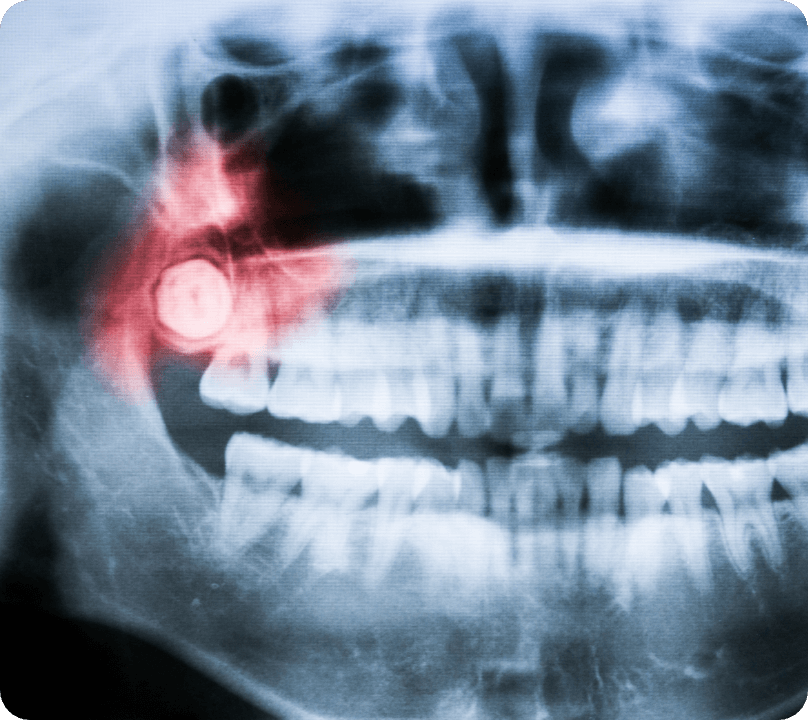

親知らずが深い、横向きに埋まっているなど、通常は大学病院等の専門機関へ紹介となることが多い症例でも、状態を確認のうえ当院で対応を提案できます。必要に応じてレントゲンやCTで神経の位置も確認し、安全性を優先して計画します。

下顎の親知らずは下歯槽神経に近い場合があり、抜歯時に損傷してしまうと麻痺が起きます。感覚神経ですので口を動かしたり喋ったりすることは問題ありませんが、知覚鈍麻や痺れ感が続きます。CT等でしっかり位置を確認し、気を付けて抜歯すればほとんど起きません。